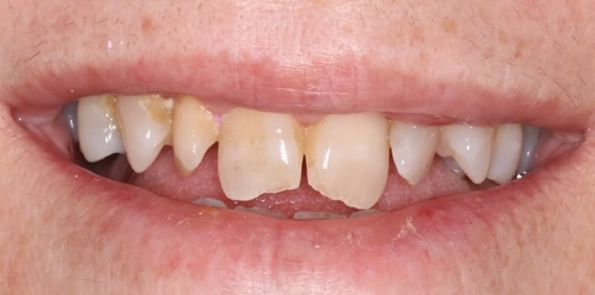

Próteses Fixa sobre dente

Tem a função de substituir um ou mais dentes perdidos ou destruídos. São próteses fixas na boca, presas sobre dentes e feitas de porcelana, podendo ser unitária ou múltipla (quando une três ou mais dentes para suprir uma ou mais ausência dentária).

Pode-se considerar também como prótese fixa, os laminados cerâmicos conhecidos como facetas e lentes de contato dental, mais indicados para o paciente que busca melhorar a estética em dentes anteriores.